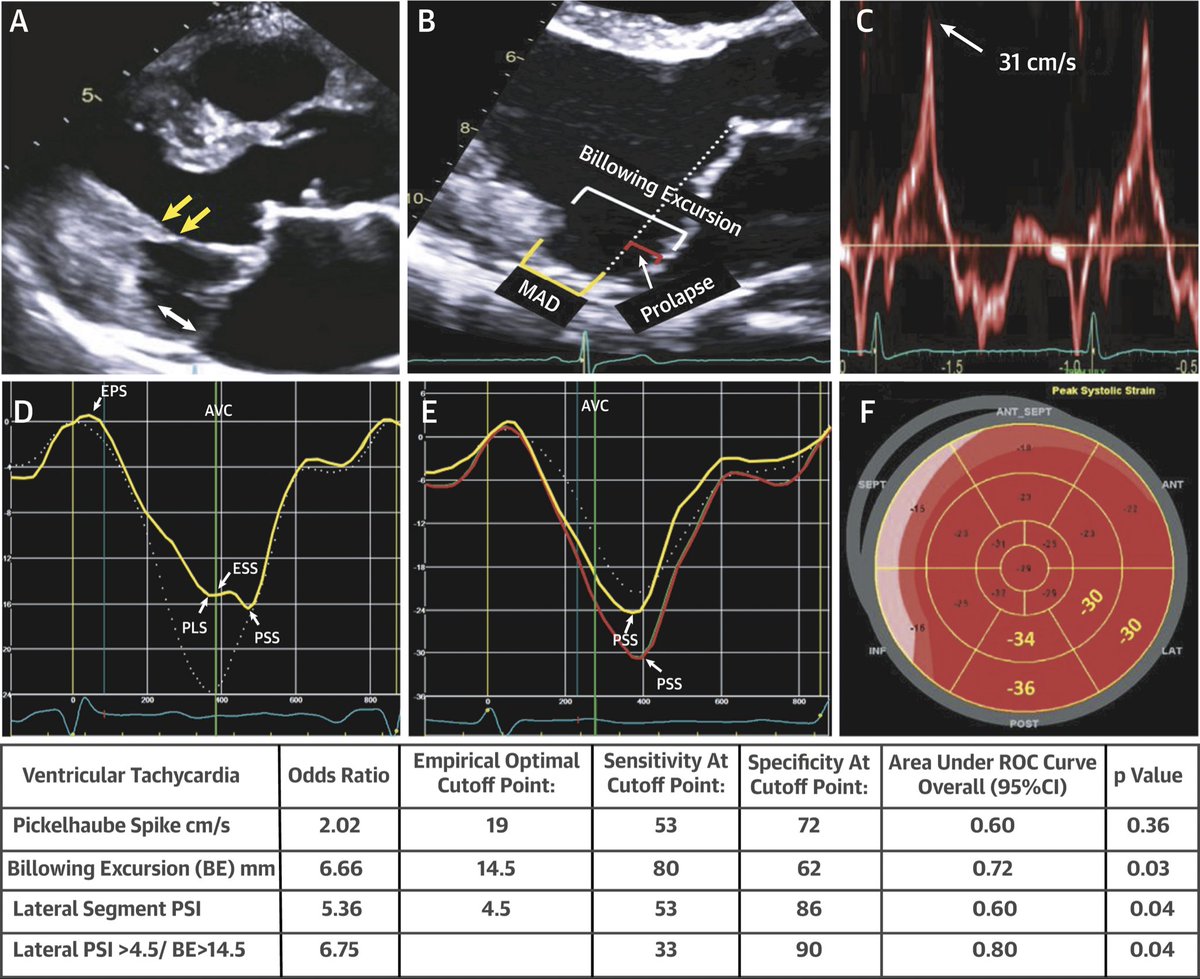

Increasing awareness of Sudden Cardiac Death In Mitral Valve Prolapse patients #Mitral Valve Prolapse #Sudden Cardiac Death Fuad Jan @JAMILTAJIK Bijoy Khandheria Patrycja Galazka Suhail Allaqaband @AuroraCVfellows

Our findings on Barlow’s MVP patients showing higher Billowing excursion values in arrhythmogenic MVP.#Malignant MVP .@Jamil_tajik Fuad Jan @AAH_StLukesCV Patrycja Galazka Bijoy Khandheria Renu